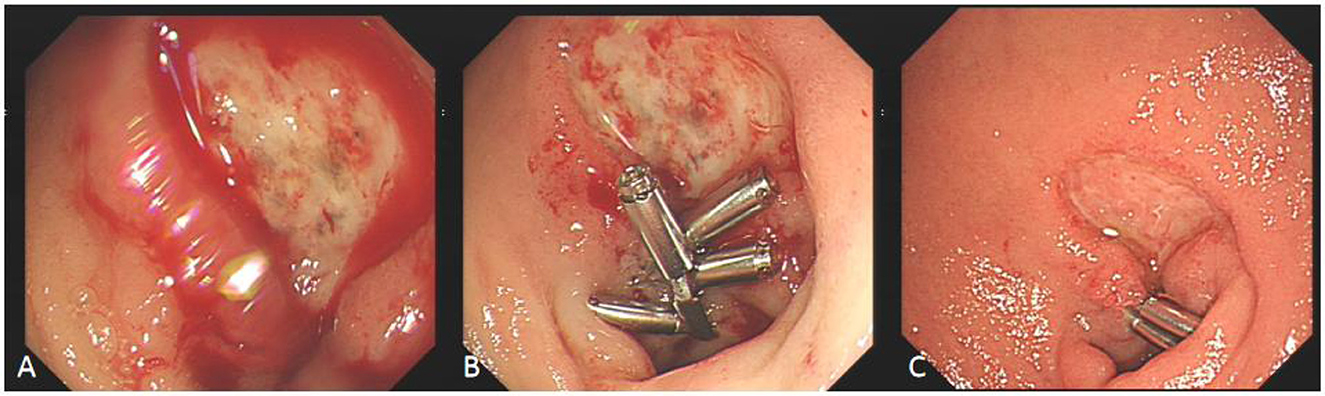

Some cases of hyperbaric oxygen therapy for refractory peptic ulcer disease (Figures 46).

Figure 4

Three endoscopic images labeled A, B, and C show a medical procedure. Image A displays a bleeding ulcer. Image B shows the ulcer with three metal clips applied. Image C shows the ulcer post-treatment, with reduced bleeding and visible healing.

Figure 4. Comparison before and after hyperbaric oxygen treatment of duodenal bulb ulcer bleeding. (A) This is a large, intractable ulcer with hemorrhage in the duodenal bulb. (B) The bleeding stopped temporarily after clamping with some titanium clamps. (C) After 2 week of hyperbaric oxygen treatment, duodenal bulb ulcer improved significantly.